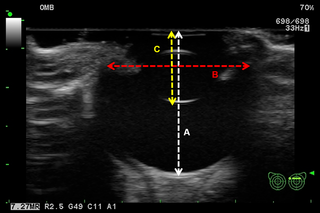

為了創(chuàng)建他們的3D打印眼球,科學(xué)家們部署了一種超聲掃描技術(shù)。然后,團(tuán)隊使用Tinkercad軟件對植入物進(jìn)行建模,并使用PCL造粒聚合物和Rokit INVIVO生物打印機(jī)進(jìn)行3D打印。